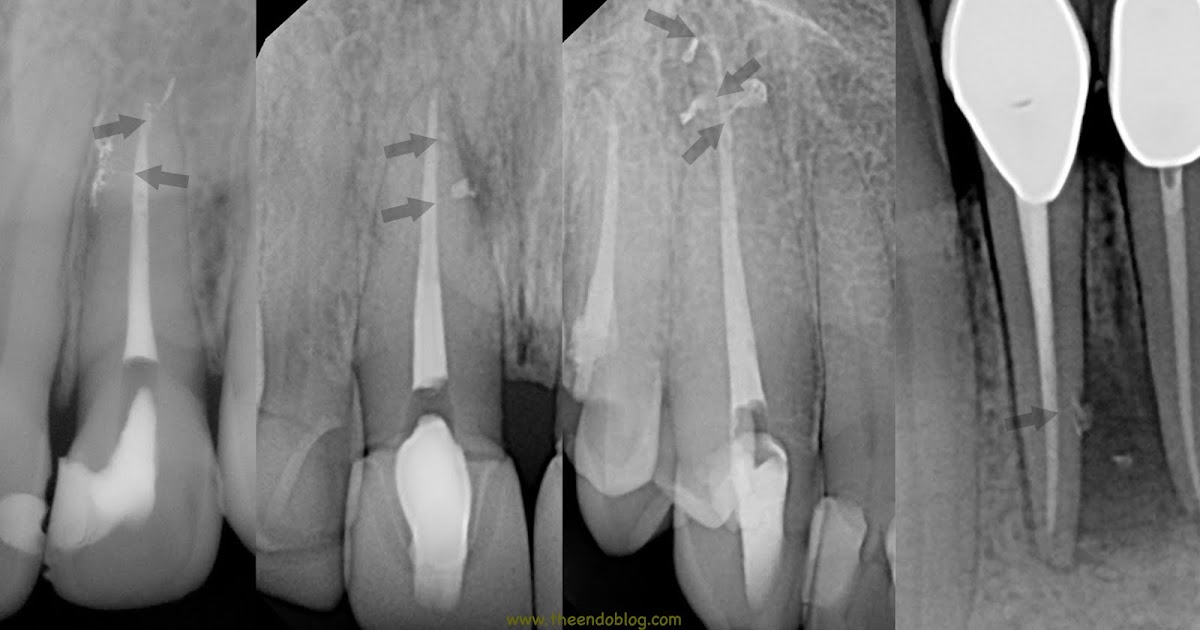

From www.theendoblog.com

The Endo Blog The Buzz About Endodontic Irrigation Endodontic Irrigation Solutions A Review The goal of endodontic treatment is to remove all the vital and necrotic tissues, microorganisms and microbial byproducts from. This review is a summary of the present knowledge of effective and safe endodontic irrigation and will include. This article reviews the new irrigants which can be used in future endodontic practice, and their advantages and limitations. In this review, potential. Endodontic Irrigation Solutions A Review.